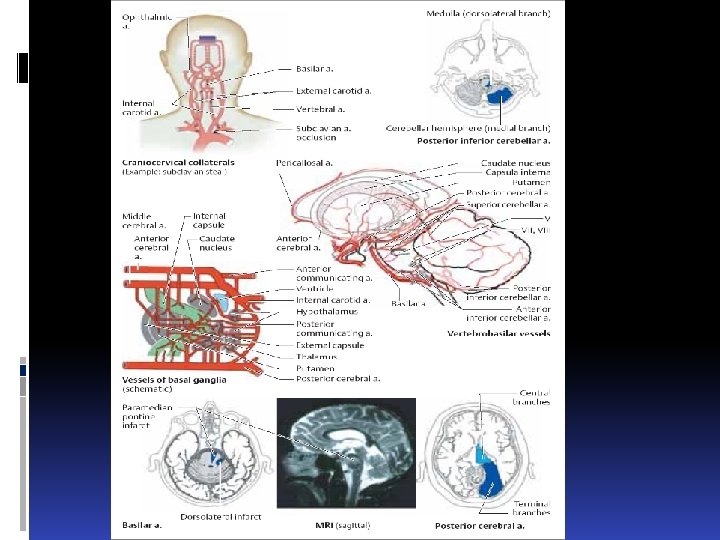

Types of infarct. There are three basic types of brain infarct, distinguished from each other by the caliber of the occluded arteries: Territorial infarcts are mainly produced by occlusions of the main trunks or major branches of cerebral arteries (cerebral macroangiopathy), which may be due to thrombosis, embolism, or other causes. The infarct includes both cortex and subcortical white matter and sometimes the basal ganglia and thalamus (Fig. 6. 12). It is usually possible to infer which vessel has been occluded from the pattern of neurological deficits that are produced.

Types of infarct. There are three basic types of brain infarct, distinguished from each other by the caliber of the occluded arteries: Territorial infarcts are mainly produced by occlusions of the main trunks or major branches of cerebral arteries (cerebral macroangiopathy), which may be due to thrombosis, embolism, or other causes. The infarct includes both cortex and subcortical white matter and sometimes the basal ganglia and thalamus (Fig. 6. 12). It is usually possible to infer which vessel has been occluded from the pattern of neurological deficits that are produced.

Наиболее частая локализация гематом: Localizations стриопаллидарная область (40%) область внутренней капсулы (16%) область зрительного бугра (10%) мозжечок (6 -10%). Striopallidar region 40% Inner capsule 16% Okular tumor area 10% Cerebellum 6 -10%

Наиболее частая локализация гематом: Localizations стриопаллидарная область (40%) область внутренней капсулы (16%) область зрительного бугра (10%) мозжечок (6 -10%). Striopallidar region 40% Inner capsule 16% Okular tumor area 10% Cerebellum 6 -10%